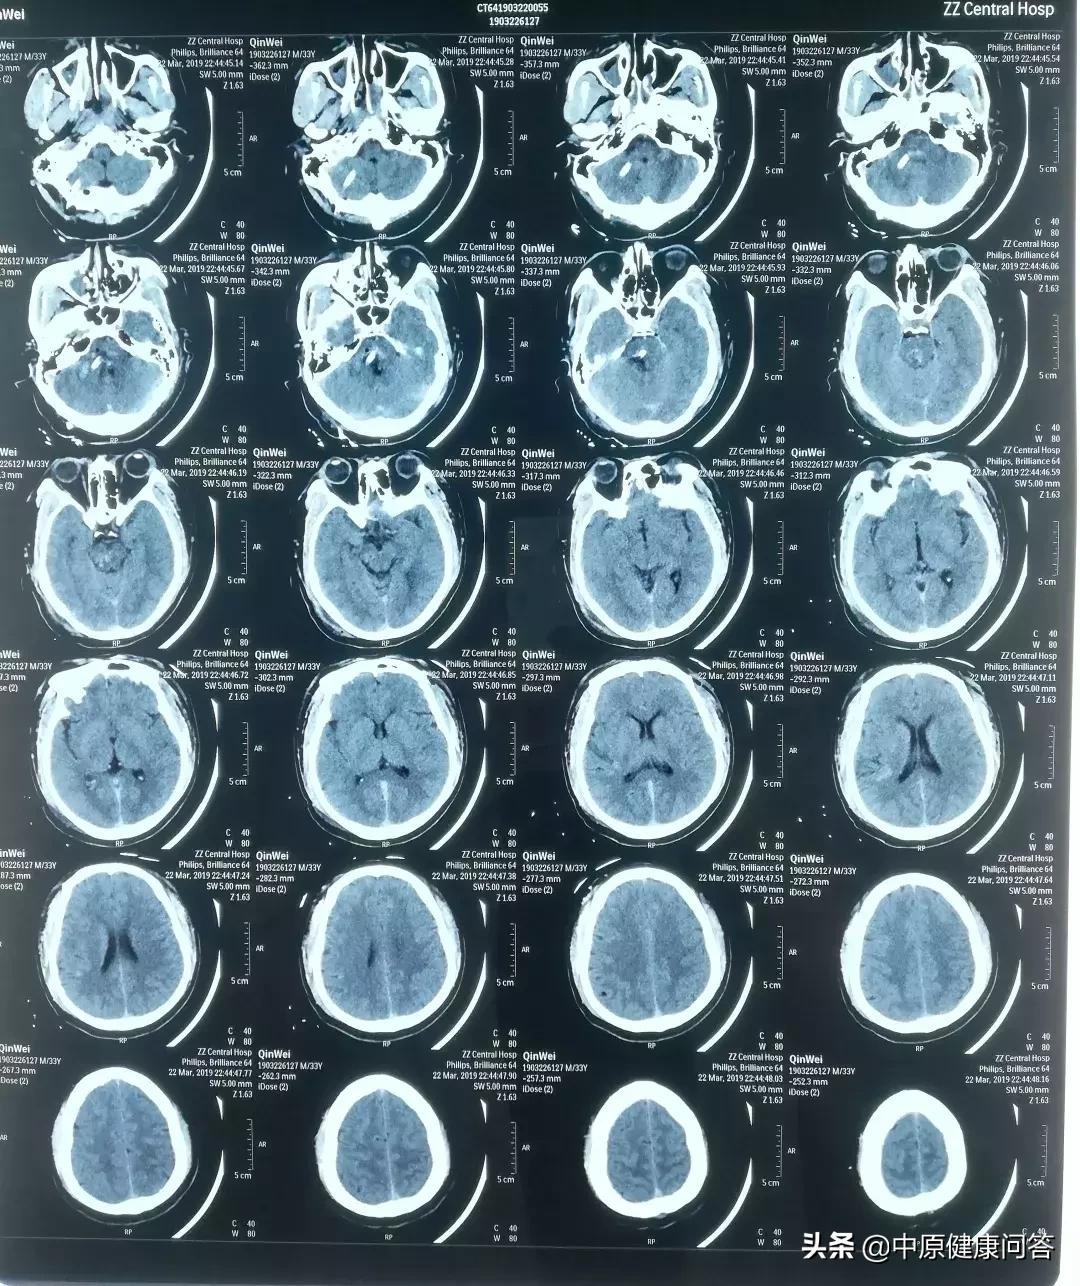

“入院后,进行了CT检查,显示患者脑干及右侧桥臂脑出血、蛛网膜下腔出血,出血量约10ml......当时就给予了患者气管插管,呼吸机辅助呼吸,病情情况危重,生存希望渺茫。”接诊的急诊科医生回忆说。

术后复查,患者血肿清除彻底,生命体征稳定。